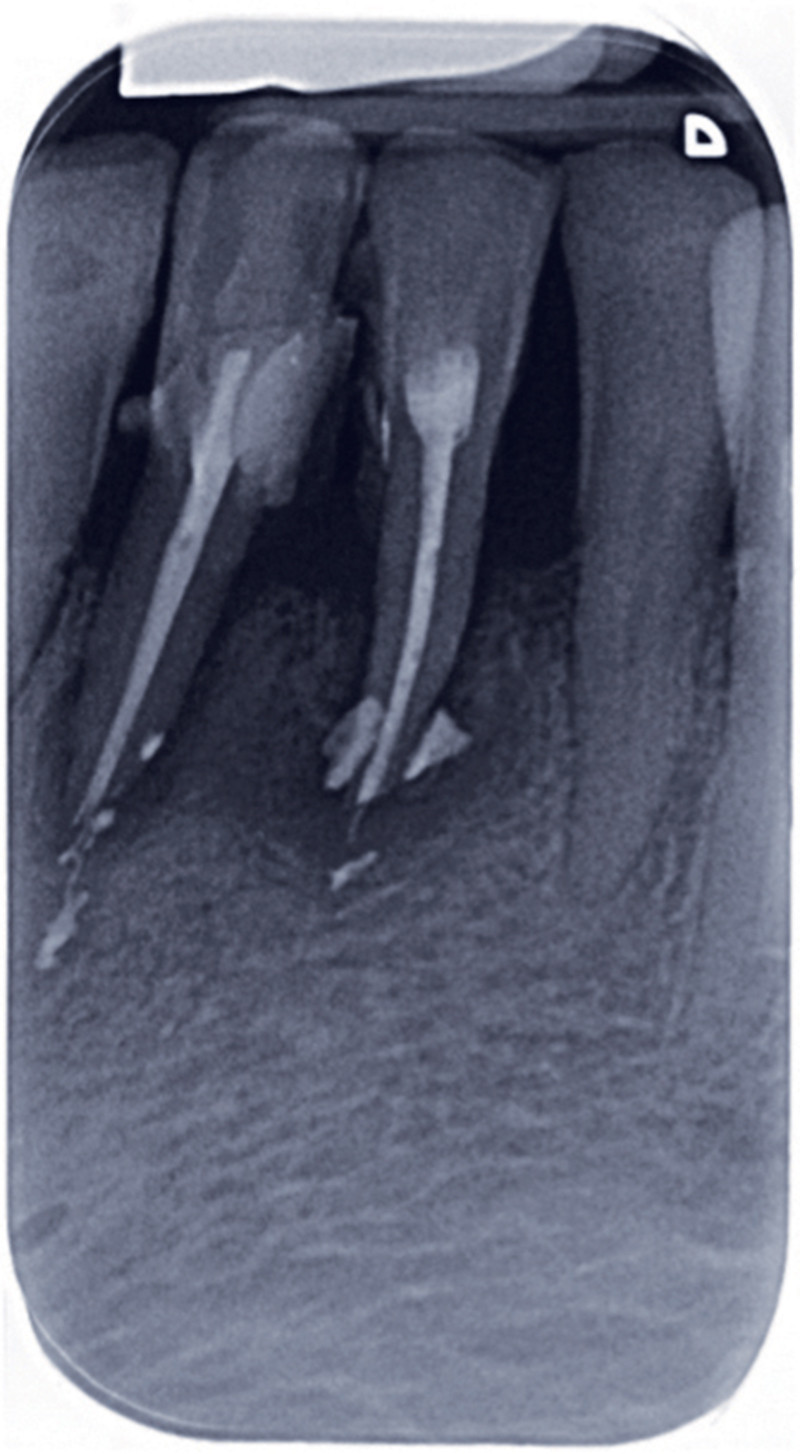

From www.researchgate.net

rétroalvéolaire;obturation endodontique descanaux mésiauxpar Obturation Endodontique There are many different materials and techniques. Once cleaning and shaping is complete the clinician must obturate the canal. This publication is intended to. Following thorough root canal debridement and disinfection, obturation serves to prevent bacteria, bacterial products and. Preparation and obturation of all root canals. For example, this particular study guide provides a summary of key papers in the. Obturation Endodontique.